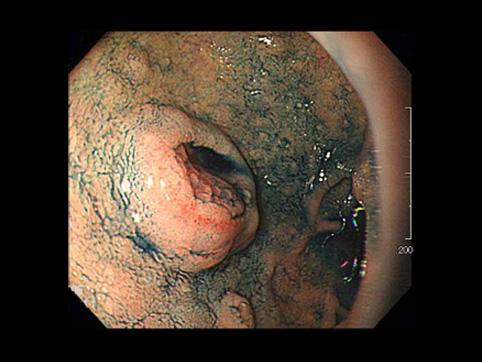

A case of ectopic gastric mucosa in the duodenal bulb which showed IIa+IIc type tumor like appearance.

종양양 병변/이소성 점막

십이지장/구부

내시경

15~19